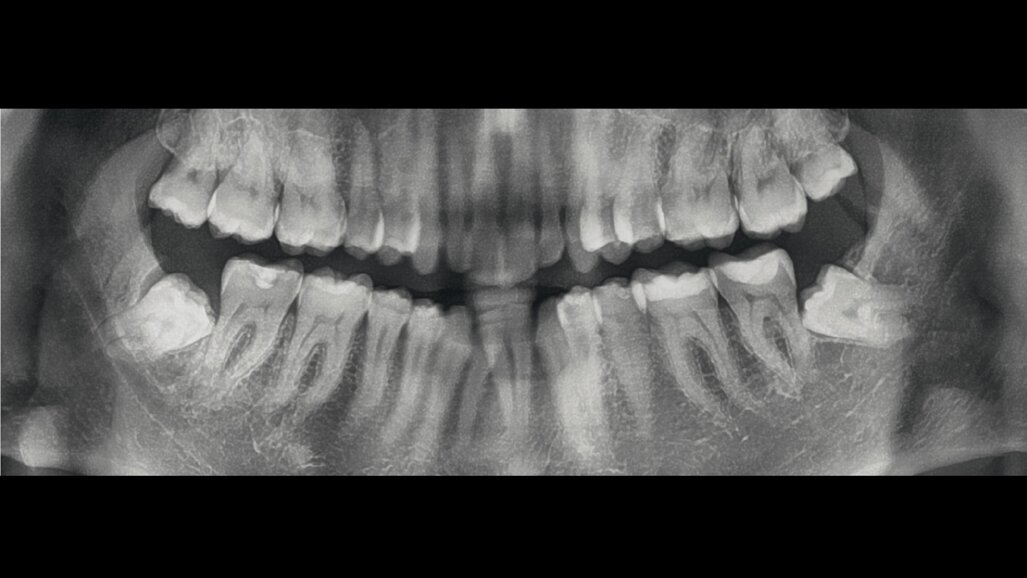

Diagnosi ed eziologia Un uomo sano di 39 anni si è presentato nel nostro studio ortodontico lamentando un aspetto dentale poco attraente e la paura della chirurgia ortognatica proposta da un altro ortodontista. Clinicamente, il profilo del paziente era rettilineo e la vista frontale non mostrava alcuna asimmetria facciale. L’esame funzionale non ha rivelato alcuna deviazione mandibolare o riduzione dei movimenti. Il paziente non aveva dolori articolari e non sono stati rilevati rumori articolari. Era presente una lieve occlusione molare bilaterale di Classe II, un morso aperto e un grave affollamento in entrambe le arcate. L’affollamento era particolarmente grave nell’arcata mandibolare, sebbene mancasse l’incisivo centrale mandibolare destro. Gli incisivi mascellari erano di piccole dimensioni, suggerendo una discrepanza dell’indice di Bolton se fossero stati presenti tutti e quattro gli incisivi mandibolari. Erano inoltre presenti un morso incrociato nella regione dell’incisivo laterale superiore sinistro e una grave rotazione distale del secondo premolare mandibolare sinistro (Figg. 1-8).

Figg. 1-8_Fotografie facciali e intraorali pre-trattamento.

Dal punto di vista parodontale il paziente ha mostrato una buona attitudine all’igiene orale, ma l’affollamento degli incisivi mandibolari ha reso difficile la pulizia in quell’area, causando un accumulo di placca e un’infiammazione gengivale localizzata. La radiografia panoramica ha rivelato la presenza dei terzi molari mandibolari e ha confermato l’assenza dell’incisivo centrale mandibolare destro (Fig. 10). L’analisi cefalometrica ha evidenziato una malocclusione scheletrica di Classe II (convessità del Punto A: 4,9 mm), una posizione leggermente retrusa del mento (profondità facciale: 78,1°) e una tendenza scheletrica al morso aperto (altezza facciale inferiore: 53,19°; asse facciale: 80,58°; Fig. 9). Gli incisivi mandibolari erano inclinati lingualmente (Li-APog: 9,3°) e retrusi (Li-APog: 1,55 mm), con un angolo interincisivo aumentato di 142,9°.